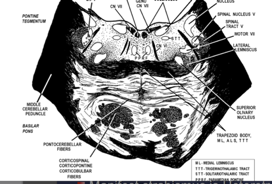

Lower Pons

SLICE 5: Lower pons—main features- abducens nucleus, facial nucleus, spinal trigeminal nucleus, superior end of vestibular complex (don’t need to resolve individual vestibular nuclei). Trapezoid body, superior olivary nucleus, corticospinal fibers, pontocerebellar fibers, middle cerebellar peduncle